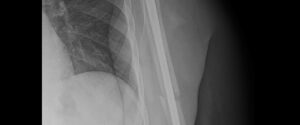

Frattura omero

Frattura omero La riabilitazione dopo una frattura dell'omero è fondamentale per recuperare la piena funzionalità dell'arto. Il processo di riabilitazione può variare a seconda della gravità della frattura, dell'età del paziente, e del tipo di intervento chirurgico (quando necessario) e [...]

Dott. Jodi Bertarelli